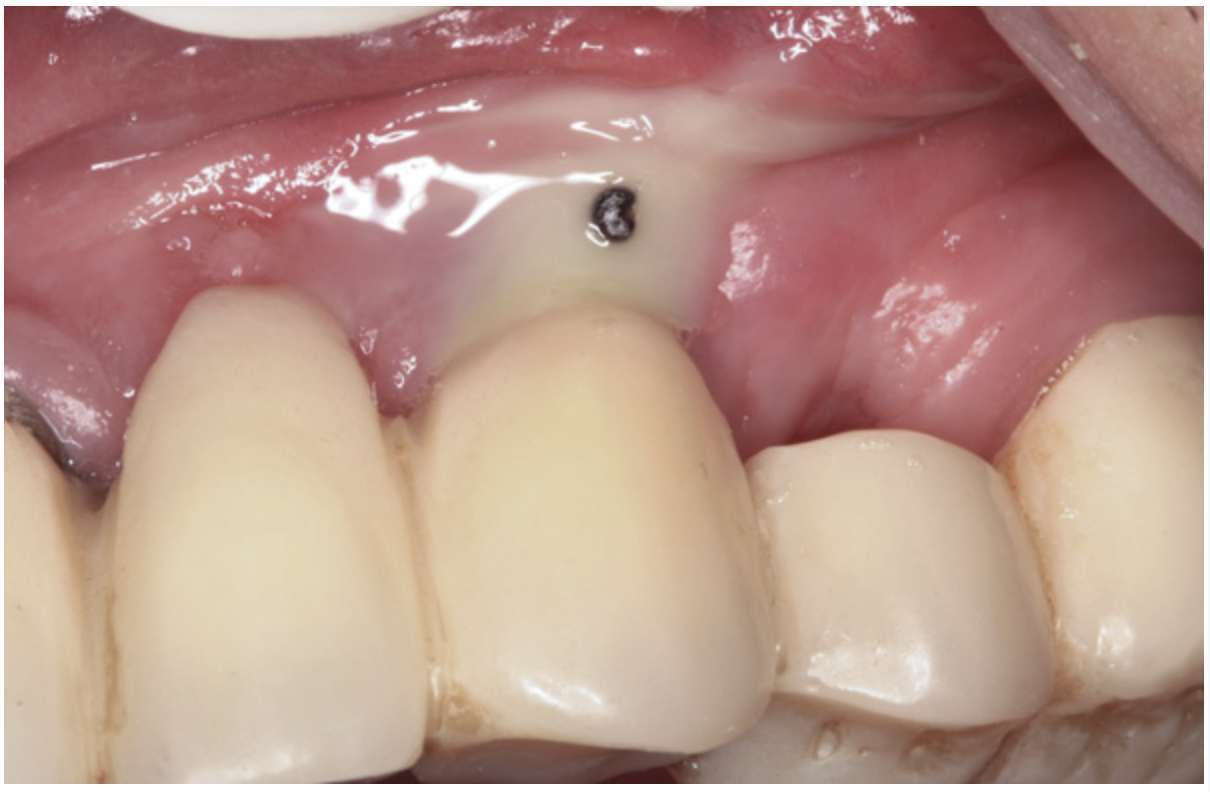

Manifestations of acute infection include abscess and cellulitis. Abscess is an accumulation of pus in an enclosed space7 (Figure 1), while cellulitis is a diffuse inflammatory process within tissues, which may manifest edema, redness, pain, and interference with function (Figure 2). With cellulitis, the infection may be caused by various organisms, and it typically occurs in loose tissues beneath the skin or mucous membranes or around muscle bundles or surrounding organs.7 Also with cellulitis, the severity of the infection is initially determined by virulence of invading bacteria and the host’s response.

Figure 1 Fistulous tract at tooth No. 30 associated with an endodontic-periodontal abscess. When palpated, the fistulous tract may express pus. Usually, a periodontal abscess will not have a fistulous tract. Its appearance usually reflects an endodontic etiology causing the lesion. (Photograph courtesy of Dr. Mehmet Dikman.)

Figure 1